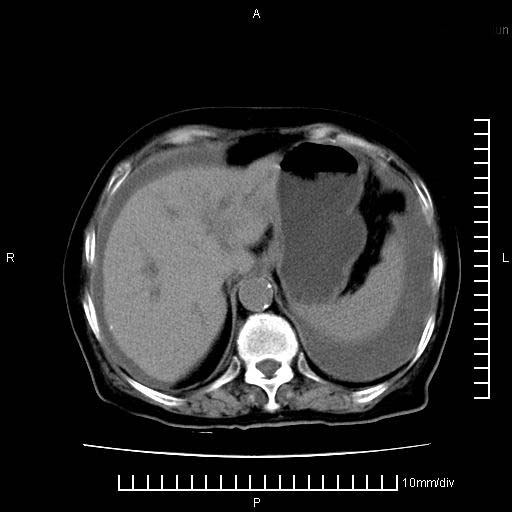

标题: CT28280:腹部增强:女性,80岁

上腹疼痛月余,外院核磁诊断胰腺癌。现临床示右下腹可明显触及包块,可片子上怎么没有看到?

1.胰腺颈体部癌。

2。腹腔积液。

3。右胸腔积液,伴右肺下叶部分萎陷。

4。右肾盂囊肿。

胰腺体部癌累及周围器官,腹膜、粘连

1。胰腺ca伴腹膜腔转移

2。肝左叶低密度灶,考虑转移可能

胰腺体部癌累及周围器官,腹膜、粘连,临床摸到的可能是粘的组织

支持胰腺癌肝内转移,腹水改变。

胰腺结构模糊,胰尾部见囊性包块,周围脂肪密度增高,左肾前筋膜增厚,胸水、腹水。不符合胰腺ca伴腹膜腔转移。考虑胰腺炎伴假性囊肿形成、胸腹腔积液。

右肾盂囊肿。

1、考虑胰腺癌伴腹膜腔转移,胸腹水。

2、肝脏转移可能。

3、右肾盂囊肿。

1)考虑胰腺癌并胰腺假性囊肿形成。2)肝内低密度灶,不排除转移。3)右肾盂积水。4)腹水。5)右侧胸腔积液并右肺下叶部分膨胀不全。